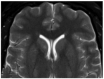

Vascular malformations are frequent in the head and neck region, affecting the nervous system. The wide range of therapeutic approaches demand the correct anatomical, morphological, and functional characterization of these lesions supported by imaging. Using a systematic search protocol in PubMed, Google Scholar, Ebsco, Redalyc, and SciELO, the authors extracted clinical studies, review articles, book chapters, and case reports that provided information about vascular cerebral malformations, in accordance with Preferred Reporting Items for Systematic Reviews and Meta-Analyses (PRISMA) guidelines. A total of 385,614 articles were grouped; using the inclusion and exclusion criteria, three of the authors independently selected 51 articles about five vascular cerebral malformations: venous malformation, brain capillary telangiectasia, brain cavernous angiomas, arteriovenous malformation, and leptomeningeal angiomatosis as part of Sturge-Weber syndrome. We described the next topics-"definition", "etiology", "pathophysiology", and "treatment"-with a focus on the relationship with the imaging approach. We concluded that the correct anatomical, morphological, and functional characterization of cerebral vascular malformations by means of various imaging studies is highly relevant in determining the therapeutic approach, and that new lines of therapeutic approaches continue to depend on the imaging evaluation of these lesions.